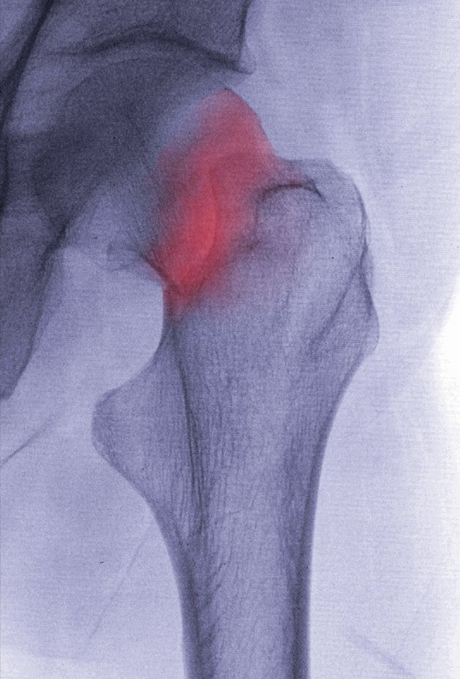

Publishing their work in the journal Nature, the team identified a genetic variant near the gene ‘EN1’ as having the strongest effect on bone mineral density (BMD) and fracture. As noted by the researchers, BMD is “highly heritable, a major predictor of osteoporotic fractures, and has been previously associated with common genetic variants as well as rare, population-specific, coding variants”.

Now, using data collected from more than 50,000 people across the world, the team has observed novel non-coding genetic variants with substantial effects on BMD and fracture. According to Associate Professor Scott Wilson, an investigator on the study from The University of Western Australia (UWA), the detailed genetic information available through genome sequencing allowed the researchers to identify rare variants associated with BMD and osteoporosis that could not have been detected by previous studies.

Osteoporosis causes bone fractures in up to a third of the world’s female population over the course of their lives, with few safe and effective treatments available. The new findings give Associate Professor Wilson and his colleagues hope that “with wider use of genome sequencing technology, we can develop a full understanding of genes associated with osteoporosis”.